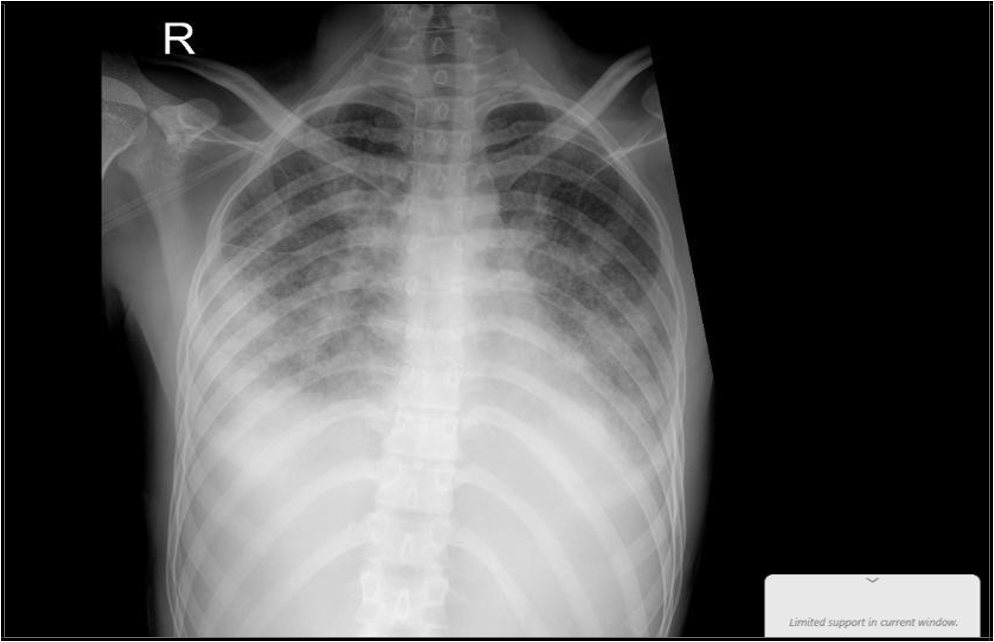

Chest X-ray

Suggestive of active pulmonary TB

(“18 Nov 2024”) Inhomogeneous opacity with a cavity formation is seen in right mid zone in para hilar region.

He started with the intensive phase of 4 medications for the 6 months anti tuberculous regime; his cough had improved, as well as follow- up lab test of CBC, electrolytes-renal functions and LFT were all normal, while CRP dropped to 8.7 and ESR to 10. The repeated chest x-ray, performed 2 weeks after initiating therapy, demonstrated mild improvement of the initial findings. The Mycobacterial culture confirmed sensitivity to both Rifampicin and Isoniazid, which supports the continued use of the standard first-line anti-TB regimen.

(“05 Dec. 2024”) Slight improvement of the opacity is seen